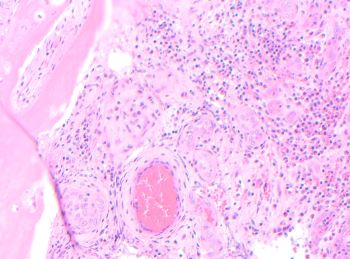

Microscopic sections show a proliferation of well-formed small blood vessels with lobular arrangement and occasionally arranged around small arteries. The small vessels are formed by epithelioid endothelial cells that display abundant eosinophilic cytoplasm and enlarged round nuclei, and normal to low nuclear-to-cytoplasmic ratio; while in more cellular areas the nuclei become elongated. The stroma is hemorrhagic to edematous with mixed inflammatory cells including numerous eosinophils, which may be a clue to the diagnosis in small biopsies.

The tumor cells express endothelial markers such as CD31, CD34, FLI1, ERG and factor VIII-related antigen. In this case, immunohistochemistry was used to demonstrate that the epithelioid endothelial cells were positive for the vascular marker ERG. Most cases show rearrangement of FOS or FOSB. The histopathologic differential diagnosis should include angiosarcoma, which is not typically well demarcated, lacks the lobular architecture, shows more cytologic atypia, and has significant proliferative activity (absent in this case). Metastatic carcinoma is negative for vascular markers. Epithelioid hemangioendothelioma shows hyalinized or chondroid stroma and vacuolated cells